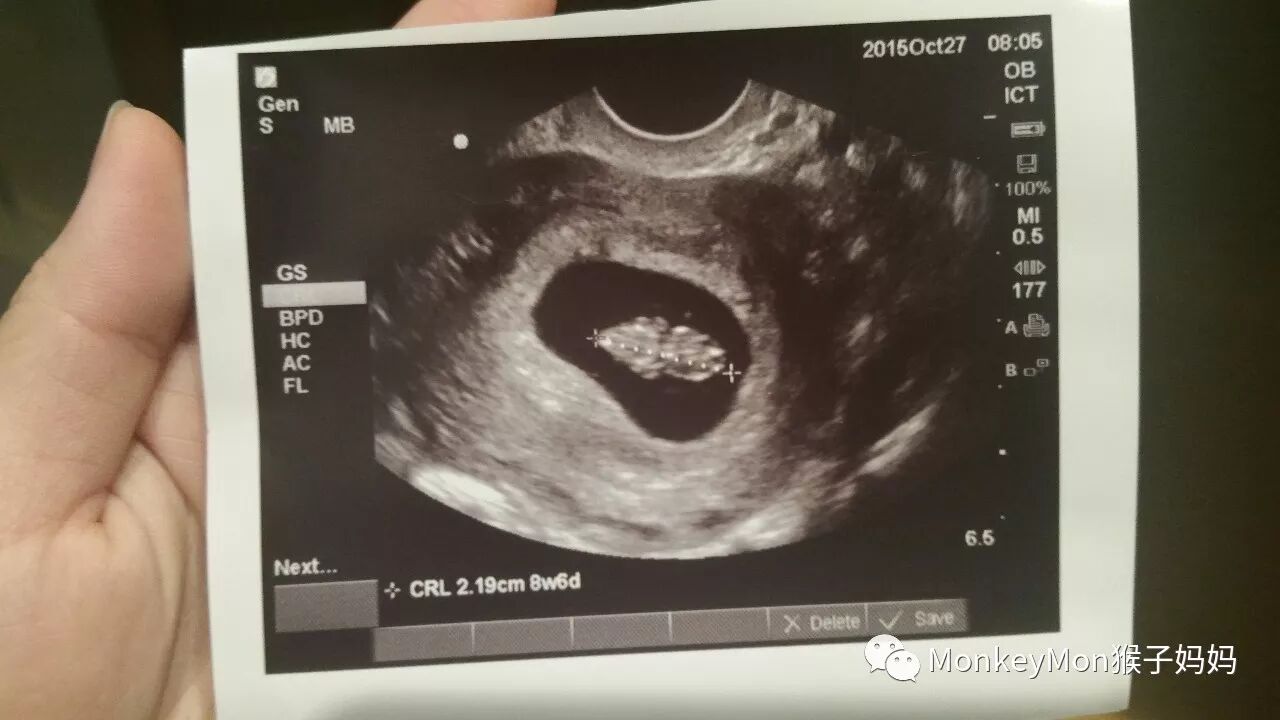

那时我们刚好在加州一号公路自驾旅行,天气挺热的,一路大吃大喝,跑跑跳跳,到了洛杉矶我开始觉得天气这么这么热,热到难以忍受,回到芝加哥以后就测了验孕棒,一算便发现已经怀孕一个多月了!欣喜若狂的我们马上预约了医生,而美国的妇产科医生(OB-GYN / Obstetrician-gynecologist)一般在孕妇怀孕8周左右才开始接受预约检查。

去了以后,医生给我们做了B超,看到了芝麻一样大的小登登,可爱极了,便迫不及待地想知道他是不是健康。医生给我们预约了血液检查,早在孕龄13周左右就可以筛查胎儿唐氏综合症和胎儿的性别,也因为我携带有地中海贫血的基因,我和老公分别在医院做了基因携带的检测。好在测试结果出来,我们没有携带共同的疾病基因,于是,还算安心顺利的孕期就这样开始了。